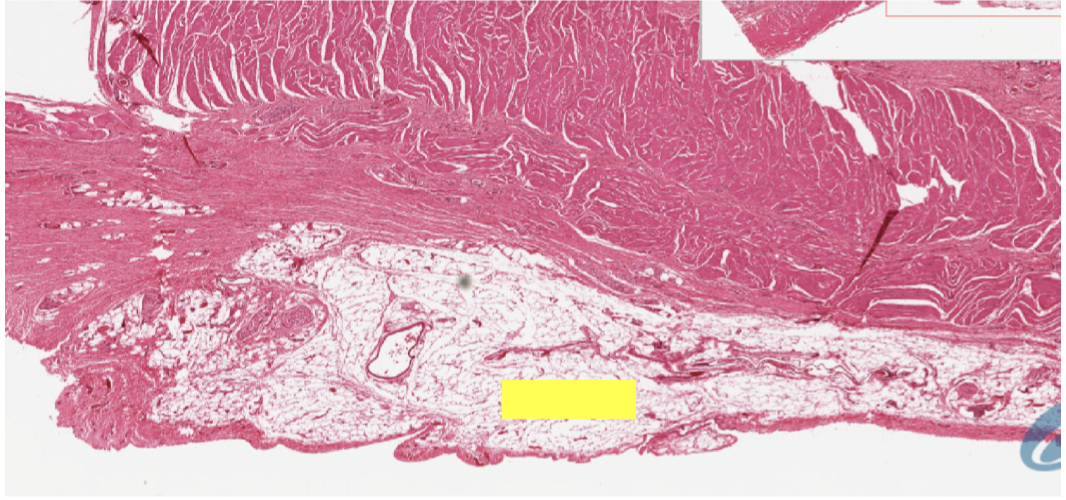

organization of tissue layers of GI tract